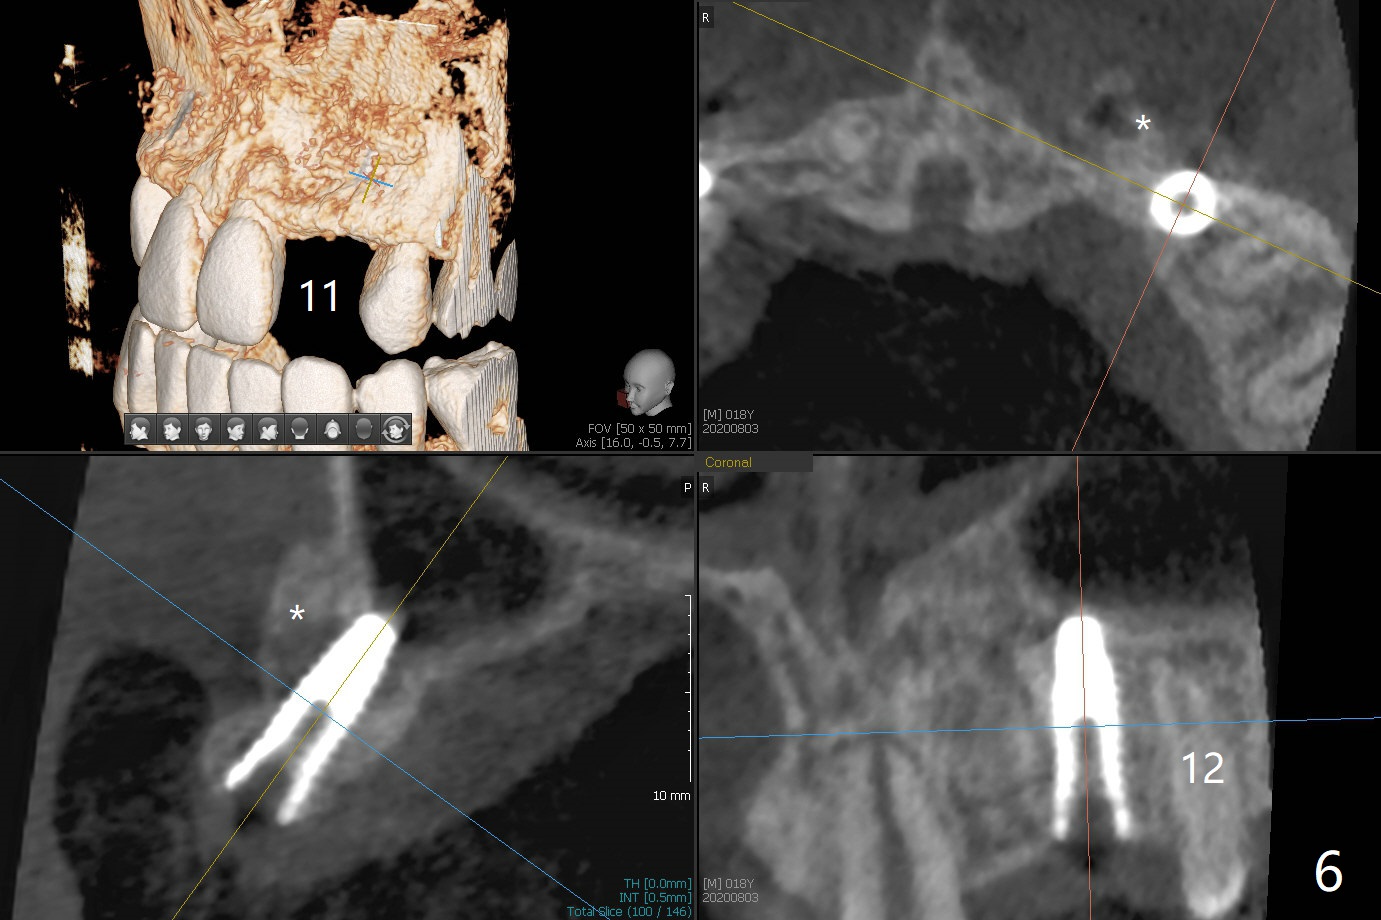

18岁男,本月底到外州上大学,急于十九岁前完成治疗,保险可以多付些。术前检查显示双侧尖牙(图一,二 6,11)根尖,侧切牙牙槽嵴萎缩(*),尖牙、侧切牙之间颊侧做垂直切口,骨膜下潜行分离,在尖牙根尖隧道植骨,然后使用导板,植入窄植体(图四至六),接近或者穿过上颌窦底板(图三,四箭头),骨粉(粘性骨块做的不成功,图五,六 *)好像覆盖暴露的螺纹。再次补充隧道骨粉后,放置修复基台(图七,八),调整后(图九),取模做临时悬臂桥,临床上有些困难分配尖牙,侧切牙比例。术后4个月左侧植体愈合正常(图十,十一),而右侧感染。